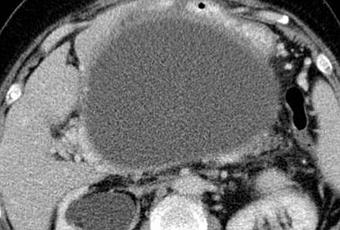

Pseudoquistes : se desarrollan después de 4 semanas; Recogida de líquidos peripancreáticos o remotos encapsulados.